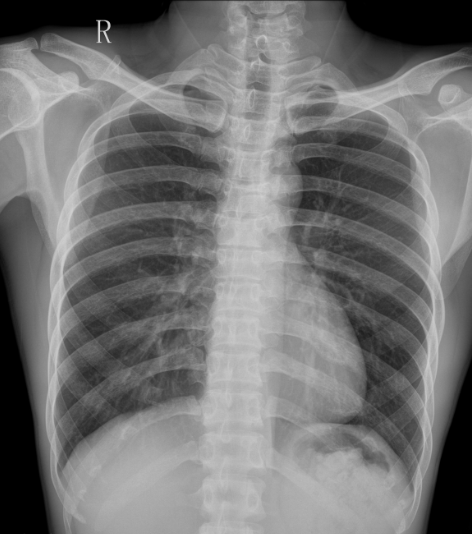

DR胸部影像图

方案介绍

DR胸部影像图,即胸部数字化X线摄影(Digital Radiography,简称DR)图像,是医学影像学中常用的一种检查手段,用于评估胸部结构、诊断肺部及胸腔疾病等。